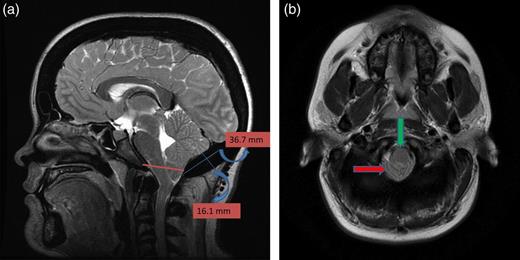

A 25-year-old female patient presented with 1-year history of occipital headache. The headache was increasing with coughing, sneezing and bending over. She had also complaints of intermittent bilateral hand numbness and bilateral feet burning. She was evaluated with magnetic resonance imaging (MRI), which showed Chiari I malformation with a 7 mm descent of cerebellar tonsils (Fig. 1 a and b). Computed tomography demonstrated diffuse calvarial thickening and loss of the medullary space (Fig. 2). Her past medical history was consistent with left eye surgery due to amblyopia when she was a child and she was blind in her left eye. Radioactive 131I treatment had been given due to the Graves’ disease and hyperthyroidism; therefore, she was hypothyroidic and was using levothyroxine daily. Her mother also was operated on because of the Chiari malformation. She had four siblings, and they did not have any pertinent medical history. Her physical examination revealed prominent occipital area and midfacial hypoplasia. Increased cortical thickness in her long bones was also demonstrated (Fig. 3 a–c). There were no abnormal findings on neurological examination except of left eye amorozis. The patient underwent surgery for decompression of posterior fossa. Large enough posterior fossa craniectomy with C1 laminectomy was performed with SSEP and MEP monitoring. Dura was opened in ‘Y’ shape, and duraplasty was performed with the pericranium. Arachnoid was kept intact. Her headaches improved significantly in postoperative period. She developed superficial wound infection, which was treated with simple washout and antibiotics.

(a) Sagittal T2-weighted image showing cerebellar tonsillar herniation and diffuse thickening of the occipital bone. (b) Axial T1-weighted image showing compression on the upper cervical spinal cord (green arrow) and cerebellar tonsillar herniation (red arrow).

This case is the second ADO case associated with Chiari type I, which presented with hindbrain headache and numbness on the upper extremity without other cranial nerve compression sign. MRI revealed brain stem compression, tonsillar herniation, occipital bone thickening and shallow posterior fossa. The first diagnosis was Chiari type I, but detailed history, endocrinologic and radiologic work-up yielded as an ADO, which was a final diagnosis.

Dlouhy and Menezes [7] proposed in their report that even if their report is the first case ADO with Chiari, further study is needed. In their report, the cause of the Chiari malformation in the OP explained as unclear. Hypotheses include mass effect from the significant calvarial thickening and subsequent downward tonsillar herniation. Further, occipital bone thickening may lead to a smaller posterior fossa. Moreover, the absence of the osteoclastic activity leads to underdeveloped occipital bone, and this results in a smaller posterior fossa [7].